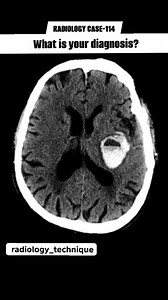

Radiology case-114 What is your diagnosis ? | Diwakar Patel

Facebook

Diwakar Patel

已浏览 5845 次

5 个月之前